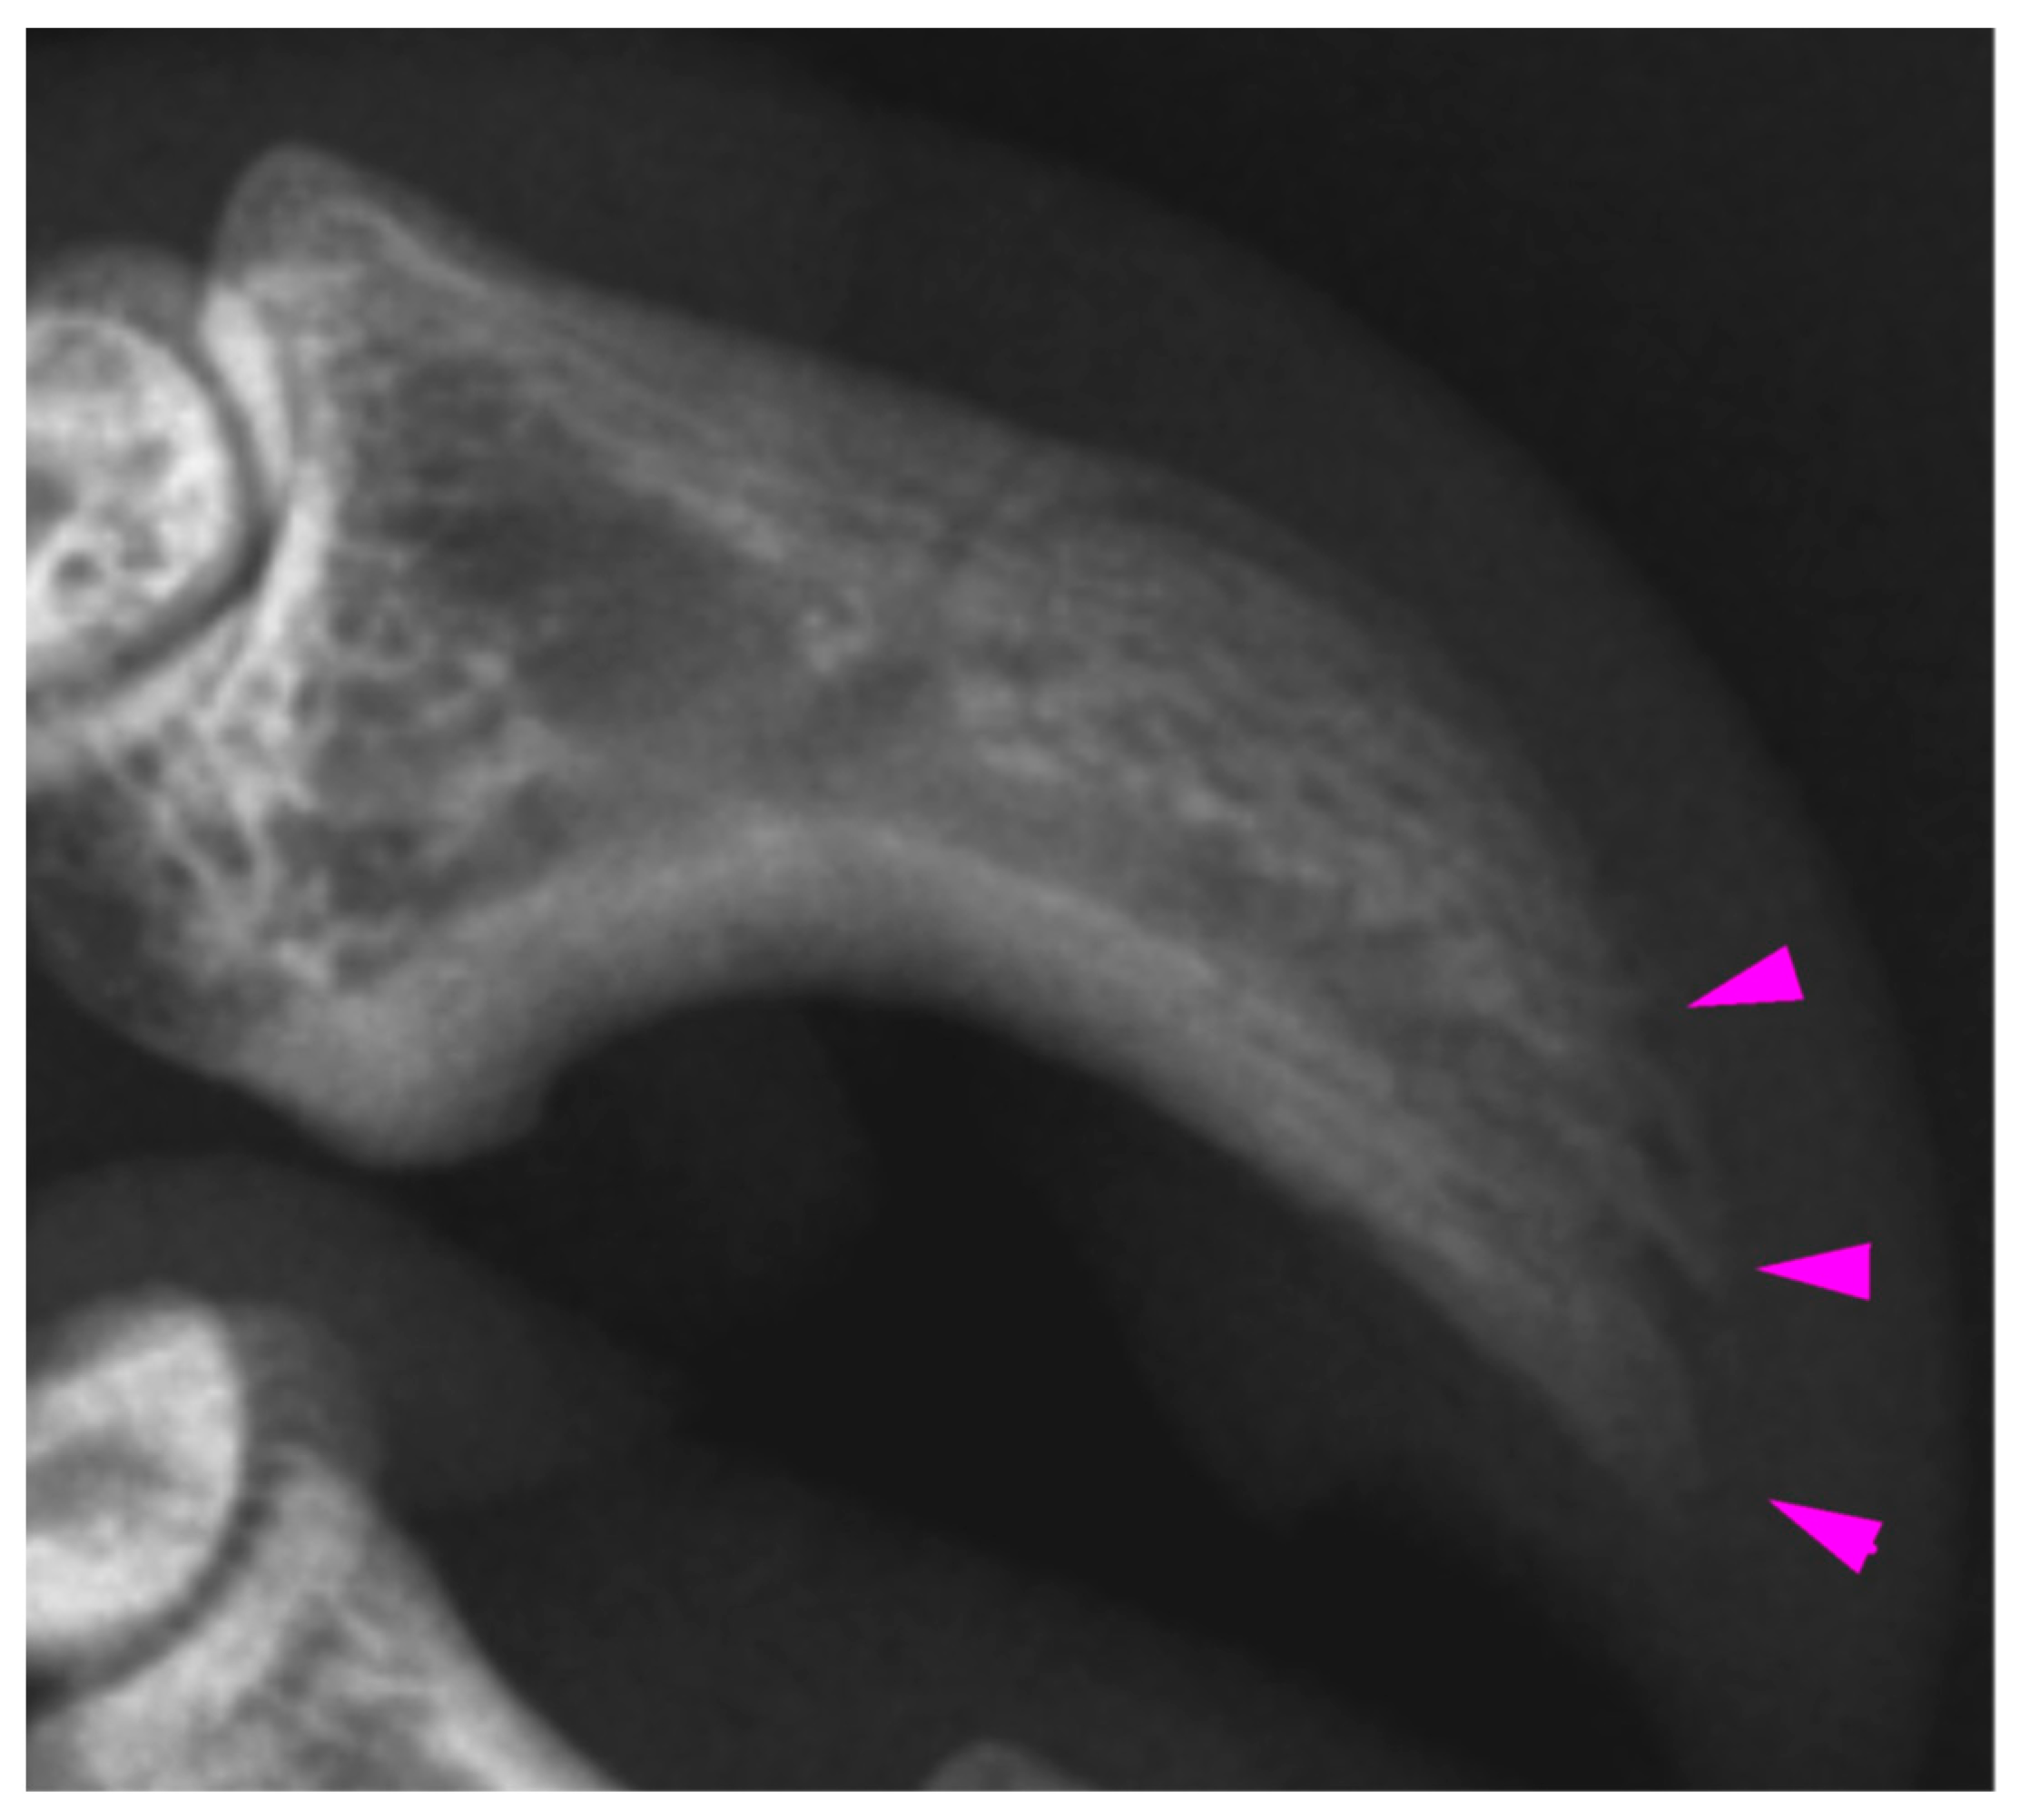

Radiologic examination of the digits of K21-047 showed mild acro-osteolysis of the distal phalanx of digits III and IV (Figure 5) of the right fore limb, with the claw of digit IV having previously been noted at necropsy to have mild erythema on the concave surface. In both hind limbs, digits II and III showed irregular lytic cortices, with more marked changes distally. On the right hind, digit III and to a lesser extent, digit II, also showed sclerosis of the medullary cavity. Digit V did not show any radiographic changes despite having superficial plantar burns present at necropsy. This digit was selected for histological examination but was unremarkable. For K21-048, the distal phalanges of the hind feet showed mild lytic changes to the distal phalanges, most notable in left digits II and IV. The digits of the fore limbs were unremarkable, despite a blunted claw tip being noted at necropsy in right fore digit III. This digit was selected for histological examination but was unremarkable. For K21-050, the claw loss of left fore digit IV and the fracture of distal phalanx V on the left hind were the only radiologic findings. Histologically, associated with the claw loss from left fore digit IV, there was necrosis of the nailbed epithelium and underlying dermis and exudation of proteinaceous material in the dermis overlying the distal phalanx, indicating necrosis. Soot was present over the exposed surface of the ungual process. There were no detectable histological abnormalities found in left fore digit III despite a blunted claw tip at necropsy.

Figure 5. Mild acro-osteolysis (arrows) of the distal phalanx of right fore digit IV in K21-047. This claw showed erythema at necropsy but was not examined histologically.

The distal digits and claws were examined radiologically and histologically based on abnormalities of the claws noted at necropsy, such as blunted claw tips that appeared to be ‘melted’ and erythema. Anecdotally, claws are often lost in rehabilitating koalas in the weeks and months following footpad burns, and blunted or melted ends of claw tips have previously been observed (author obs.). Claw loss in burnt koalas mirrors that which occurs in other species, such as the loss of hooves in burnt livestock [8]. In K21-047, there were radiographically lytic and sclerotic changes to the distal phalanges in those digits noted to be abnormal at necropsy, supporting the presence of heat radiation damage to the underlying ungual process and more proximal bone. However, these digits were not examined histologically, and in K21-050, in which one claw was lost from the ungual process of left fore digit IV, there was only soot and superficial secondary infection present. Given that these koalas were euthanised within the week following the fire, it may be that clinically observable changes due to damage to the nailbed of the claws occur at a later stage. In humans, osteolytic changes occur over many days to weeks. As such, the full extent of radiographic changes may not have been observed as resorptive processes predominate over approximately the first two weeks following an acute burn injury [16]. For K21-050, a distal phalangeal fracture in left hind digit V could also indicate that a fall or other traumatic event could have contributed to the claw loss.